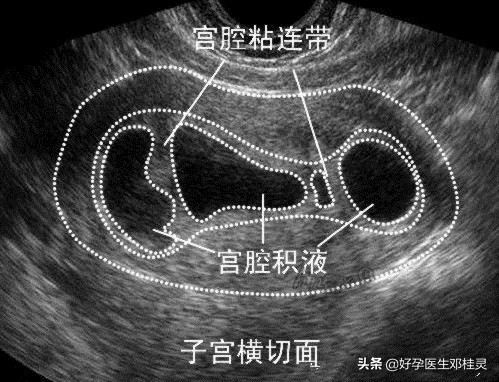

结果发现子宫内膜很薄,只有6mm,而且提示可能存在“宫腔粘连”。

其实,当女性的子宫内膜受到破坏后,并且累及到基底层,那么就无法形成功能层,随之月经量便减少,甚至闭经。内膜层受损,导致紧贴的子宫前后壁相互粘连,使子宫腔变小,严重的宫腔粘连可导致宫腔闭锁。